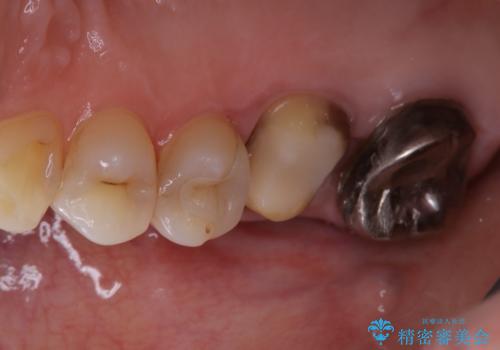

根管治療を再度行うことでフィステル(ニキビのようなできもの)は消失しました。最終的にセラミッククラウンによる補綴治療を行いました。

被せ物について

適合不良の補綴物は二次的な虫歯発生のリスクが高まります。

自費診療で用いられる材料は保険適応の材料に比べて、より精密で適合の良い被せ物作ることができるため、長期的な虫歯のリスクを大幅に減らすことが可能です。